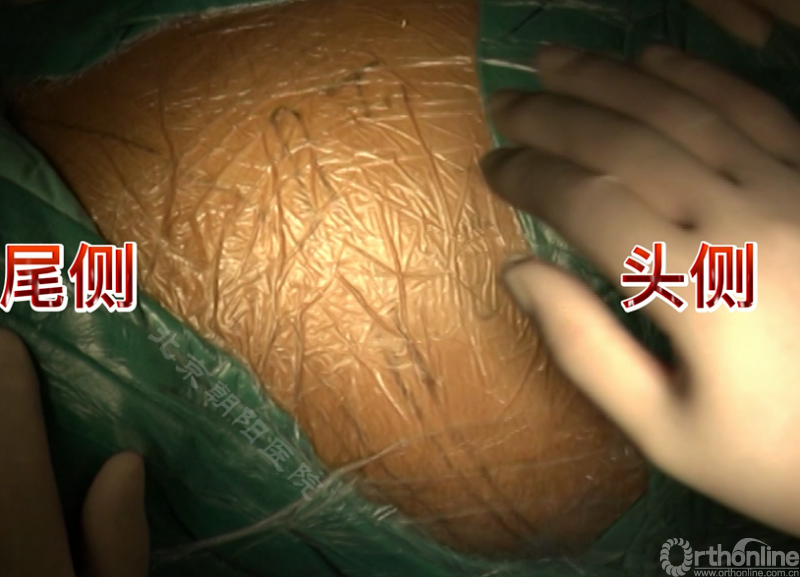

图12.前路矫正术体位摆放示例

胸腰段/腰段AIS前路矫正手术示例

患者11岁青少年女性,诊断为Lenke 5C型AIS,T10-L4 Cobb角50.5°、T5-10 Cobb角31.5°,主弯顶椎为L1,融合范围选择为T1-L3。

术者:首都医科大学附属北京朝阳医院骨科 海涌教授

经近端需内固定的椎体(T11)相对应的肋骨表面做一弧形切口,分离浅层软组织直至肋骨表面的多层肌肉组织,切口止于脐的远端偏外侧。